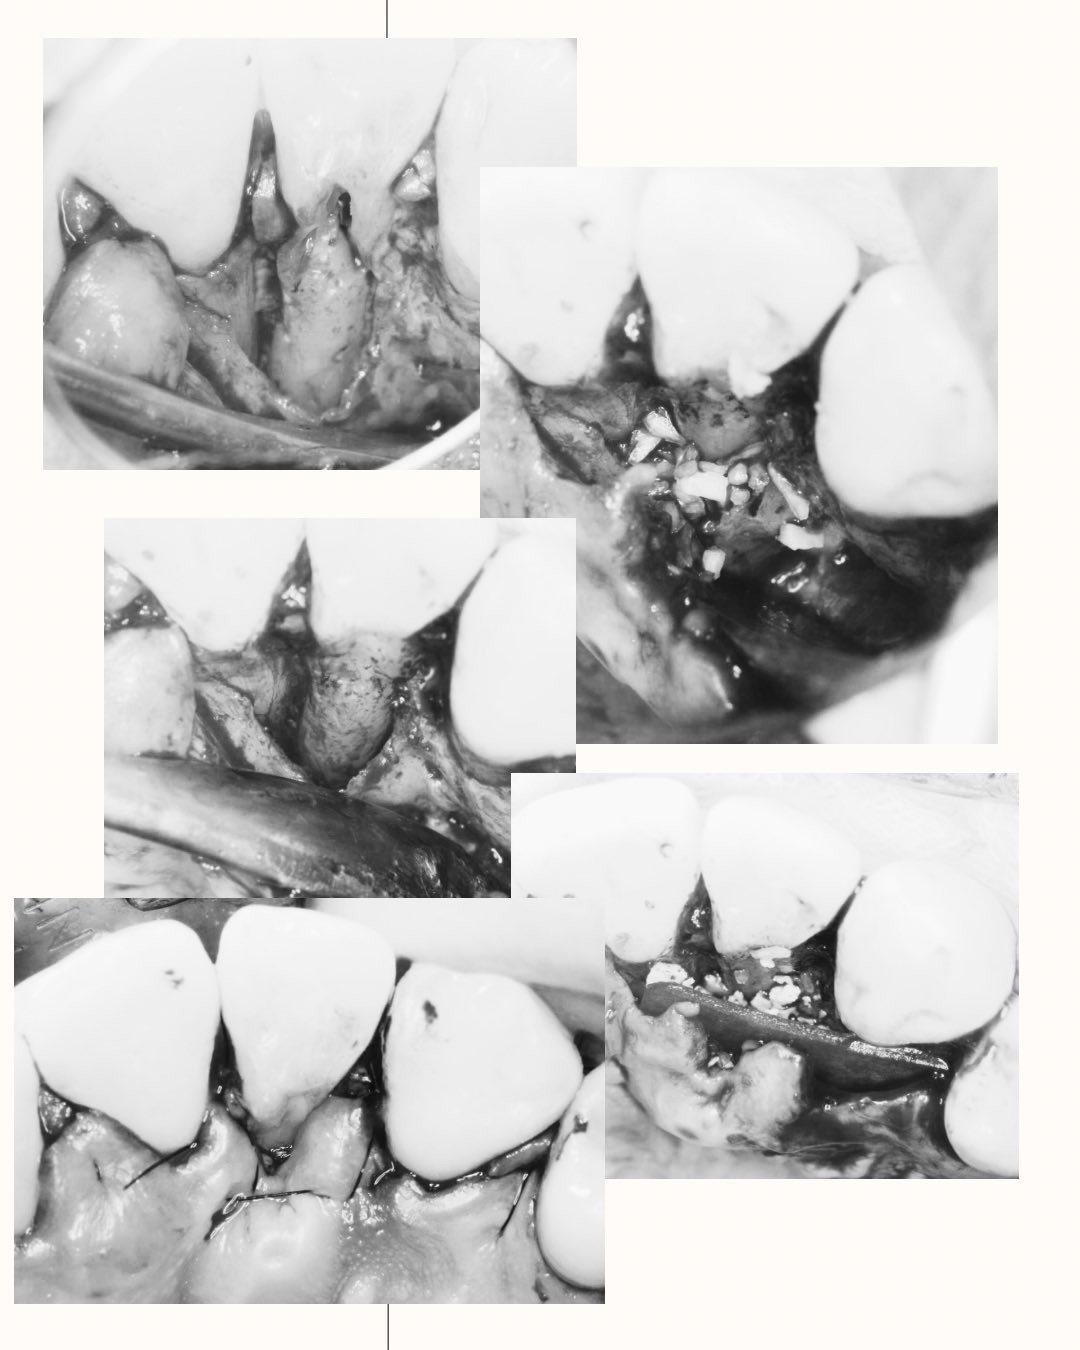

Treatment of the palato-radicular groove and cemental tear: a case report

Deep probing depth and CT scan can be done to diagnose the periodontal disease and cemental tears. Open flap surgery to remove tears of cementum and composite resin fills the groove. Then, GTR with FDBA and collagen membrane.

右上側門牙經由牙周再生手術,誘導牙周細胞的再生,修復先前受損的牙周組織。

GTR: Tetracycline + NS, Gentamicin irrigation, BioOss(s) + Lyoplant